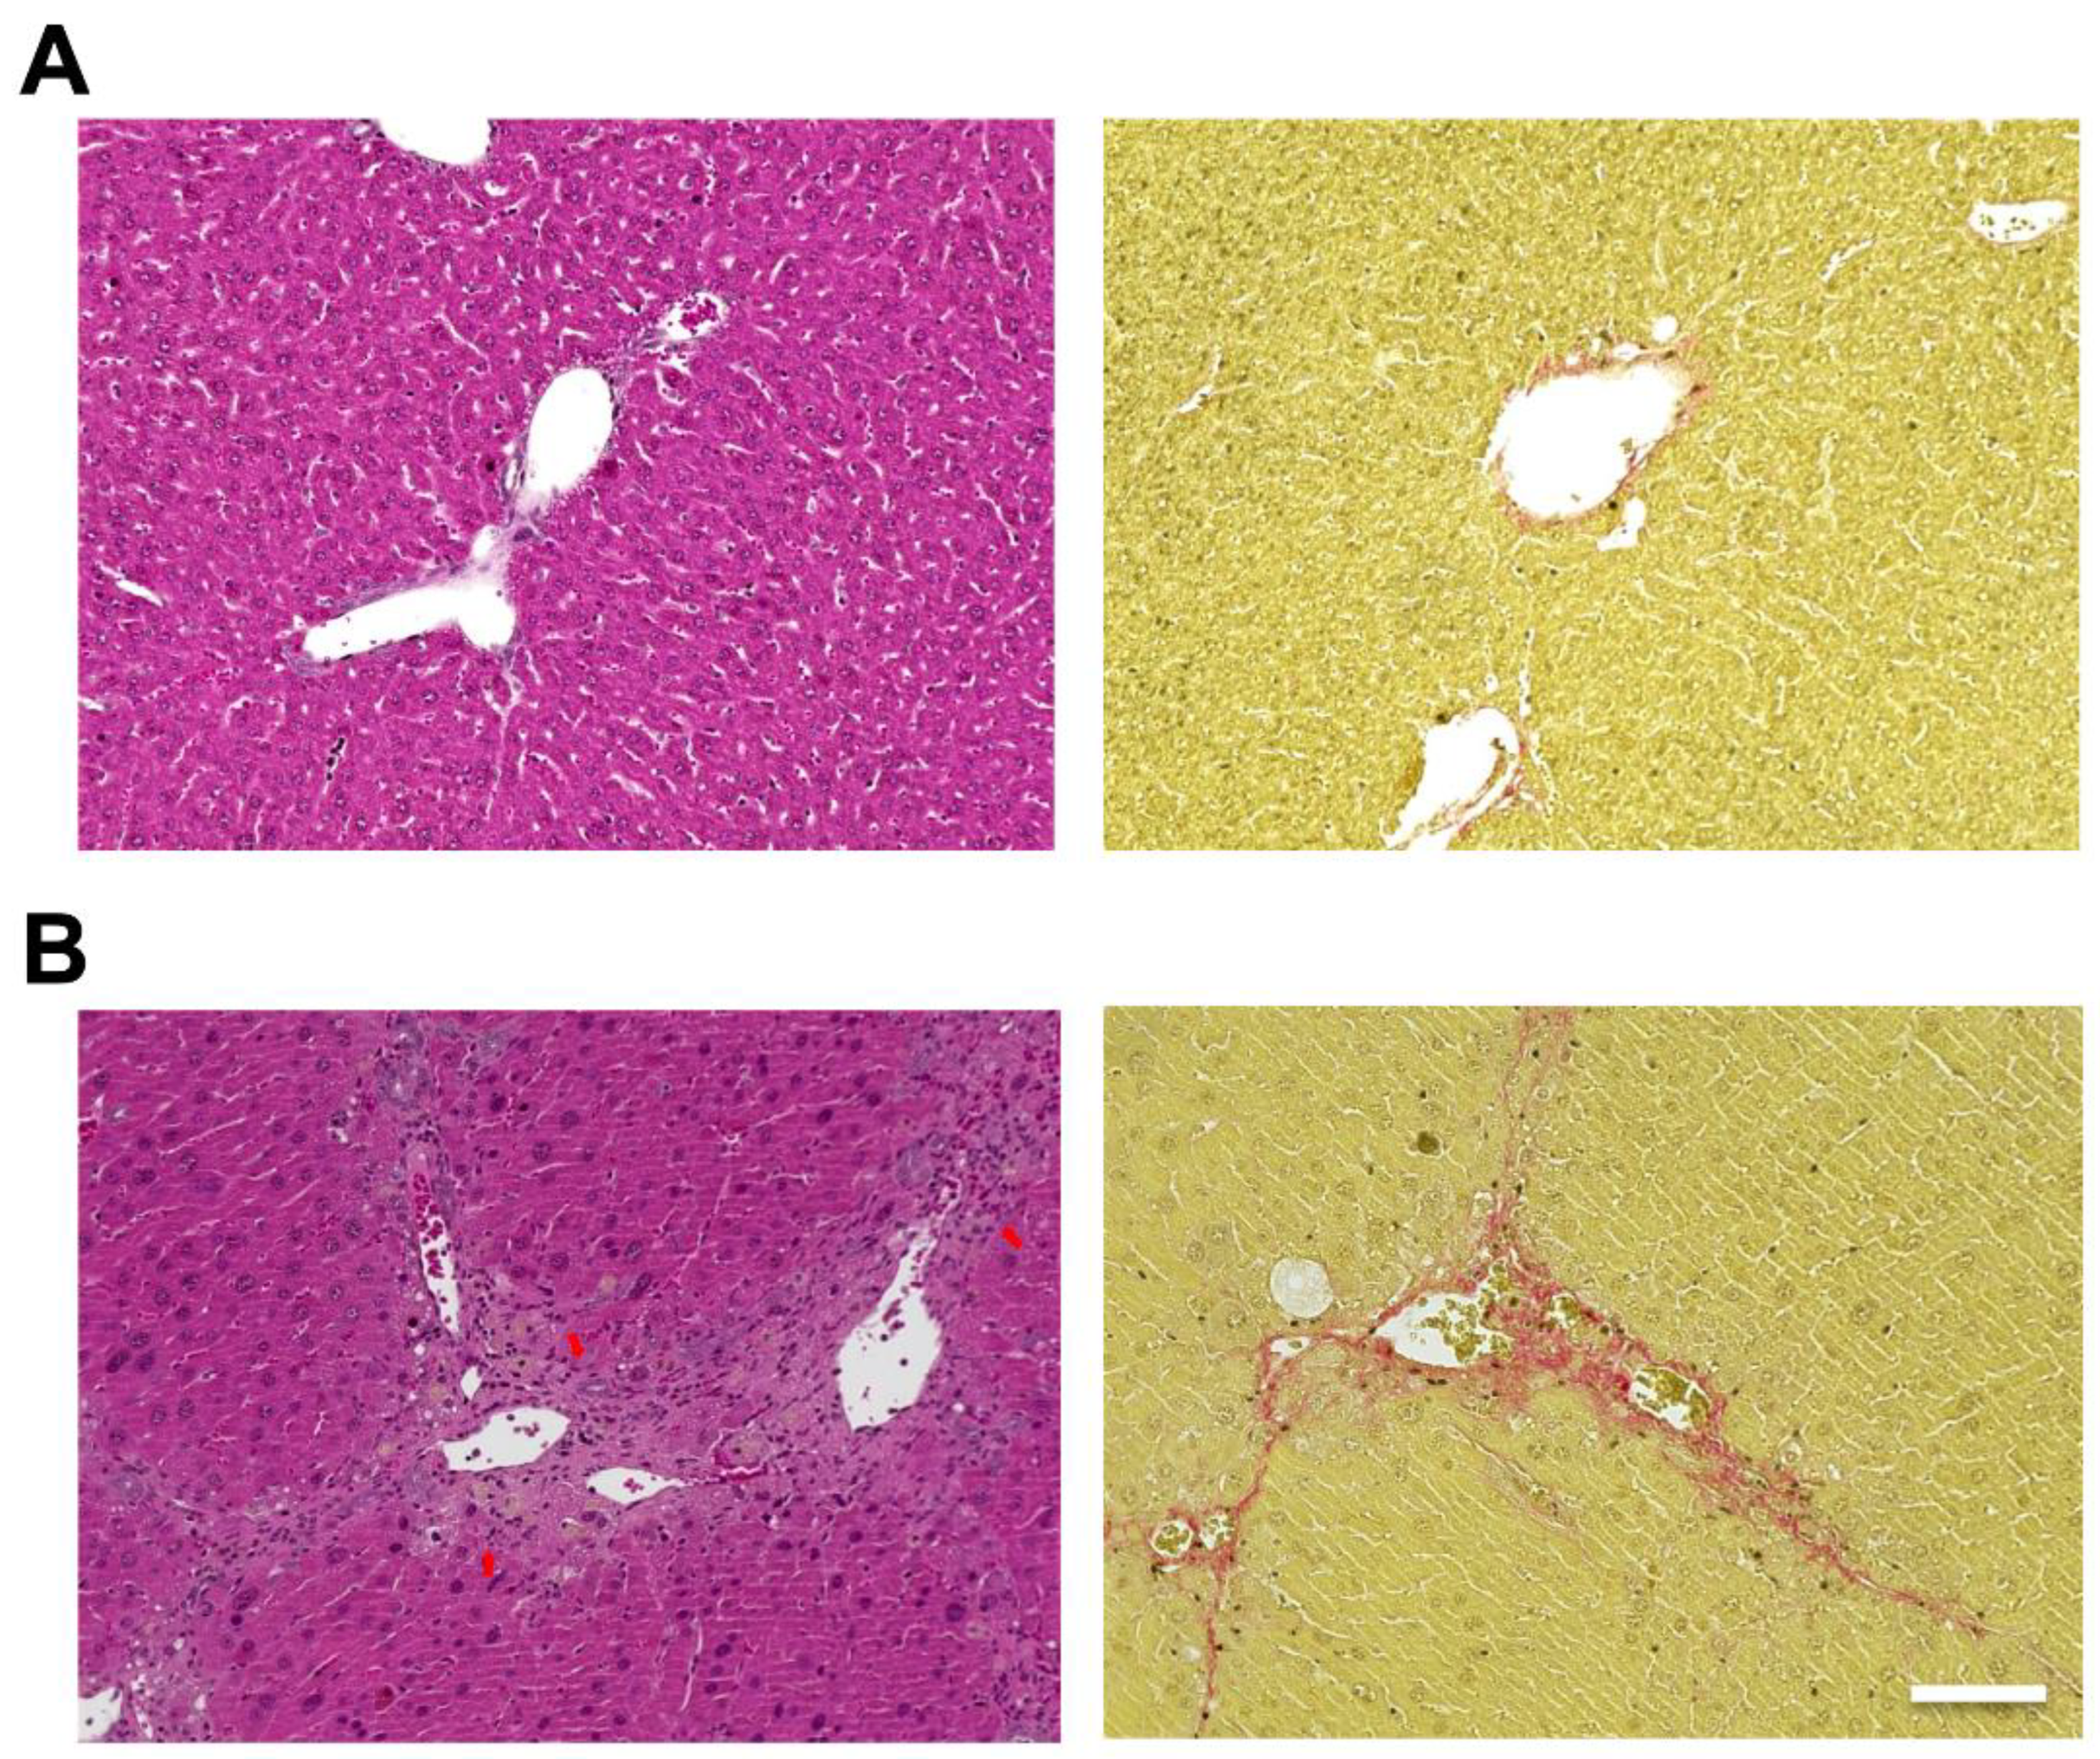

Hematoxylin and eosin (H&E) staining of the liver showed hepatic steatosis and mild hepatocyte ballooning degeneration in WD-fed mice and a significant increase in Non-alcoholic Fatty Liver Disease Activity Score (NAS) [27] (Figure 1). Hepatic tissue from a mouse model of MASH showed about 60% steatosis, moderate inflammatory cell infiltration, and ballooning of hepatocytes (NAS: Steatosis: 2, Inflammation: 2, Ballooning: 1), which are similar to the characteristics of human MASH. Sirius red staining showed mild fibrosis around the portal area. The pathological findings in the liver fibrosis model mice using CCl4 with a control diet showed moderate fibrosis primarily around the portal areas, accompanied by infiltration of inflammatory cells (Figure 2). Fibrosis was more severe in the liver fibrosis model than in the MASH model.

Figure 1.

Mouse model fed Western diet (WD) and treated by CCl4-induced metabolic dysfunction-associated steatotic liver, which develops metabolic dysfunction-associated steatohepatitis (MASH). Control mice are fed in a control diet (CD). Hematoxylin and eosin (H&E) staining of livers from (A; left) CD-fed and (B; left) WD-fed mice. Sirius Red staining of livers from (A; right) CD-fed and (B; right) WD-fed mice. Scale bar: 100 μm. Arrowheads: hepatocyte ballooning, Arrows: infiltration of inflammatory cells.